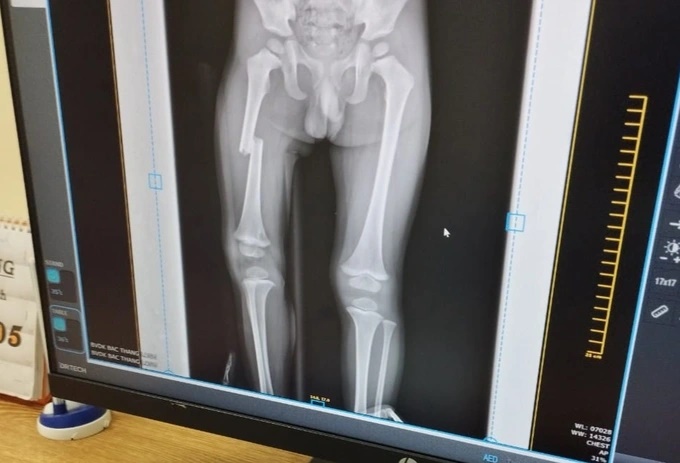

Bé trai bị gãy xương đùi. (Ảnh: X.N.)

Chú của nạn nhân cho hay, kết quả chụp chiếu cho thấy bé trai bị gãy xương đùi.